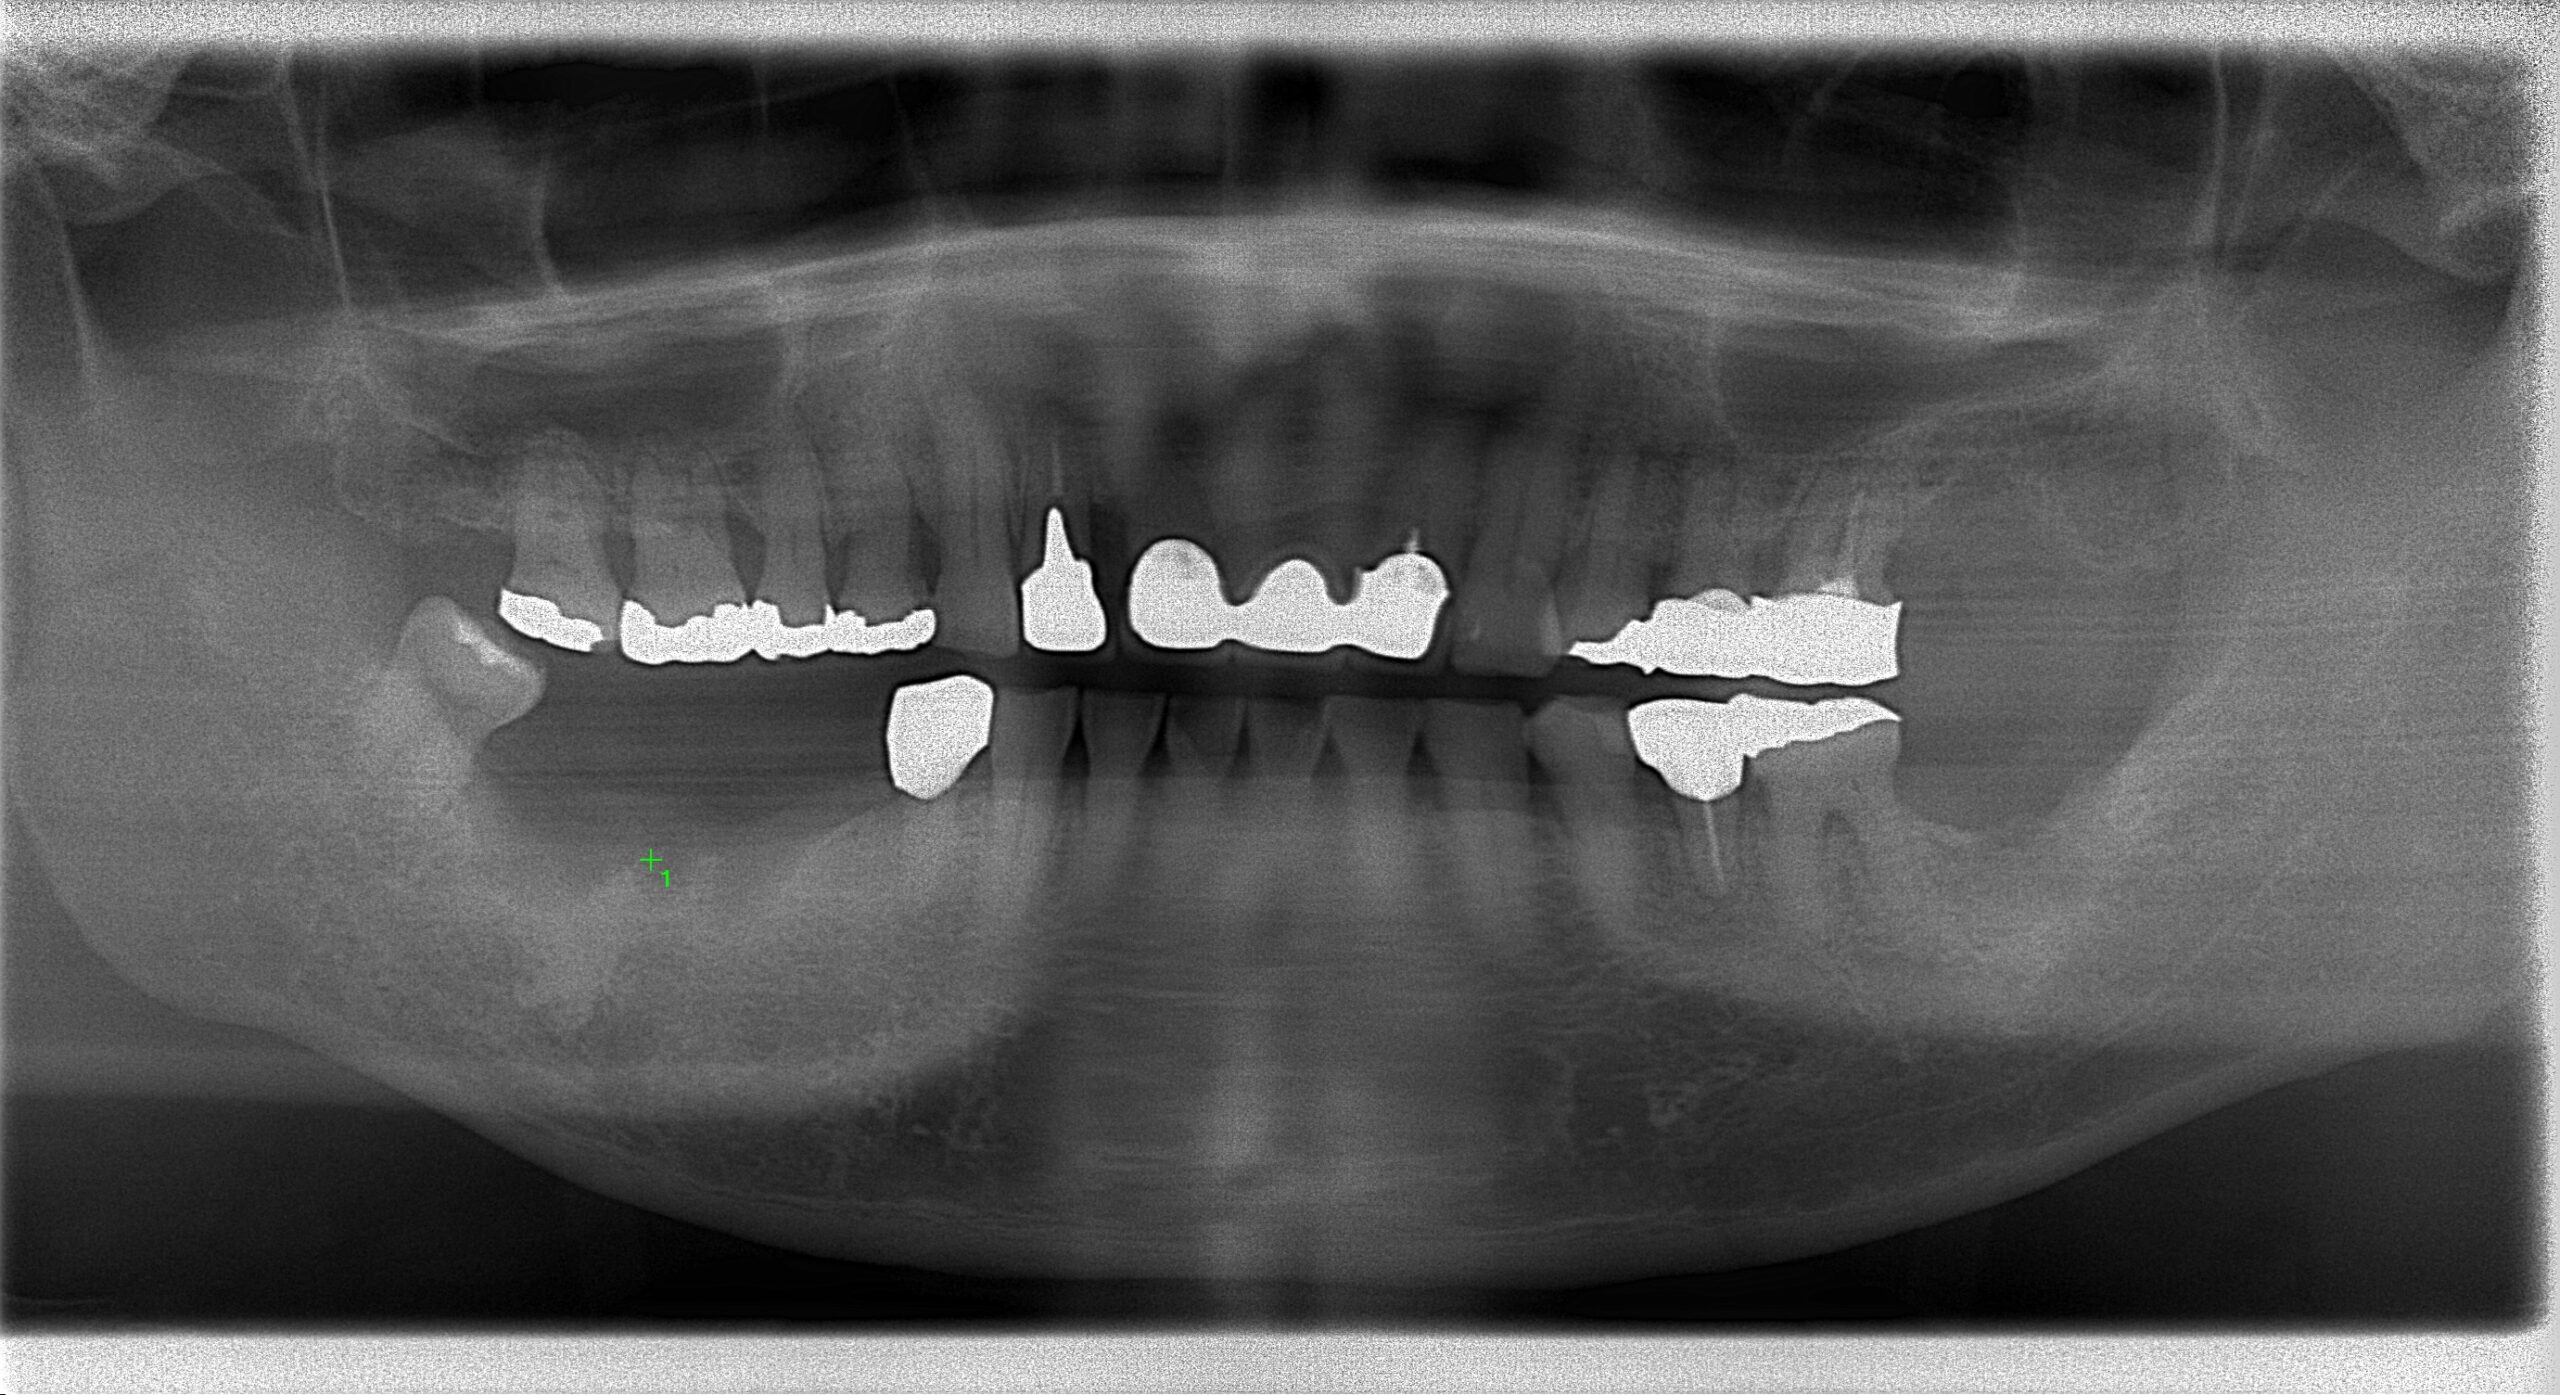

治療後

良い位置にインプラントを埋入することができました。

インプラントを入れることで反対側の歯を守る効果もございます。